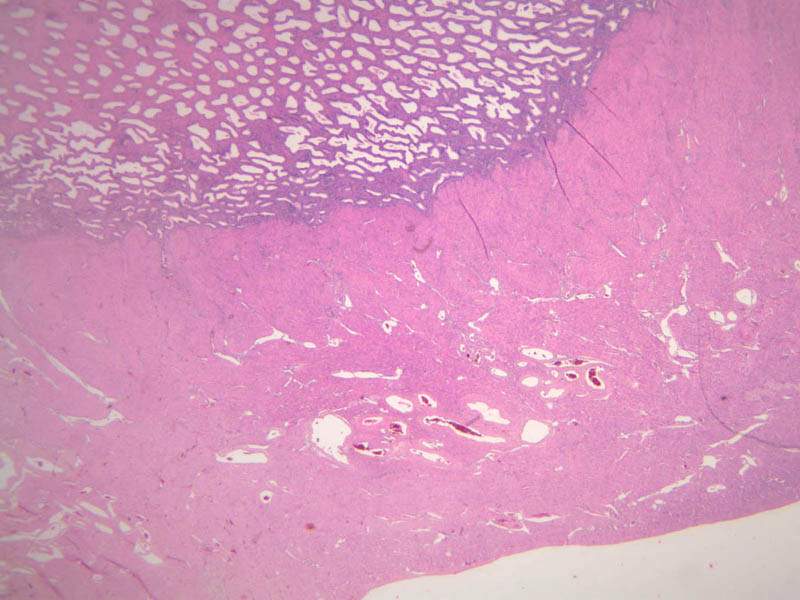

The ovary is a somewhat oval and slightly flattened organ situated near the fimbriated end of the uterine tube (B-94, monkey ovary, H&E [1x, 1x]; B-95, monkey ovary, H&E [1x-labeled, 1x]; B-96, monkey ovary and tube, H&E [1x]; B-54, H&E [1x, 1x]). Its exposed surface is covered by a mesothelial sheet of squamous or cuboidal epithelium. Just deep to this is an ill defined area of dense fibrous connective tissue referred to as the tunica albuginea (B-96 [2.5x-labeled, 10x-labeled, 20x, 40x]).

The ovary has two major regions – the cortex and the medulla. The cortex is the broad peripheral area containing follicles in various stages of development, whereas the medulla is the more central area displaying profiles of large blood vessels. These blood vessels gain entrance via the mesovarium. The division between the cortex and medulla is indistinct. In the cortex, stromal cells occupy the areas between the follicles. These cells are closely packed, fusiform (spindle shaped), and have the potential to differentiate into a specialized component of the maturing follicle (theca folliculi).